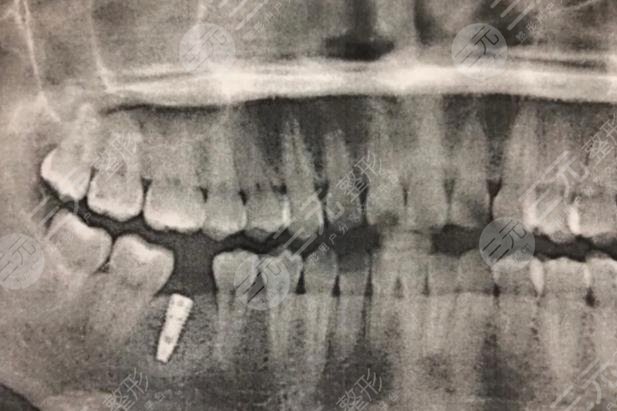

于是在朋友的陪伴下,我來到醫(yī)院,醫(yī)生親切的接待了我,醫(yī)生判斷我的牙齒已經(jīng)完全齲壞,做修復(fù)已然不可能,他建議我拿掉,然后做種植牙,種植牙降低風(fēng)險(xiǎn)系數(shù)高,使用壽命長,而且**較為的高。此前我比較擔(dān)心疼痛,但醫(yī)生給我解釋到種植牙所用的是局部mz,完全沒有疼痛感,其疼痛程度低于拔智齒。在比較詳細(xì)了解相關(guān)信息以后,我就決定在這家醫(yī)院做種植牙,而事實(shí)證明,我的決定是較為正確的,當(dāng)天我就做了拔牙,然后醫(yī)生給我定制了專門的牙冠以及種植體。

過一段時(shí)間以后就進(jìn)行種植修復(fù),誠如醫(yī)生所言,整個(gè)過程沒有明X的痛感,回去以后有麻麻的感覺。不過好在可以忍受。做完以后,我感覺吃什么都香了,對(duì)此我較為的滿意,也建議大家牙齒有問題的話,應(yīng)該盡快去處理避免錯(cuò)過好的時(shí)間。